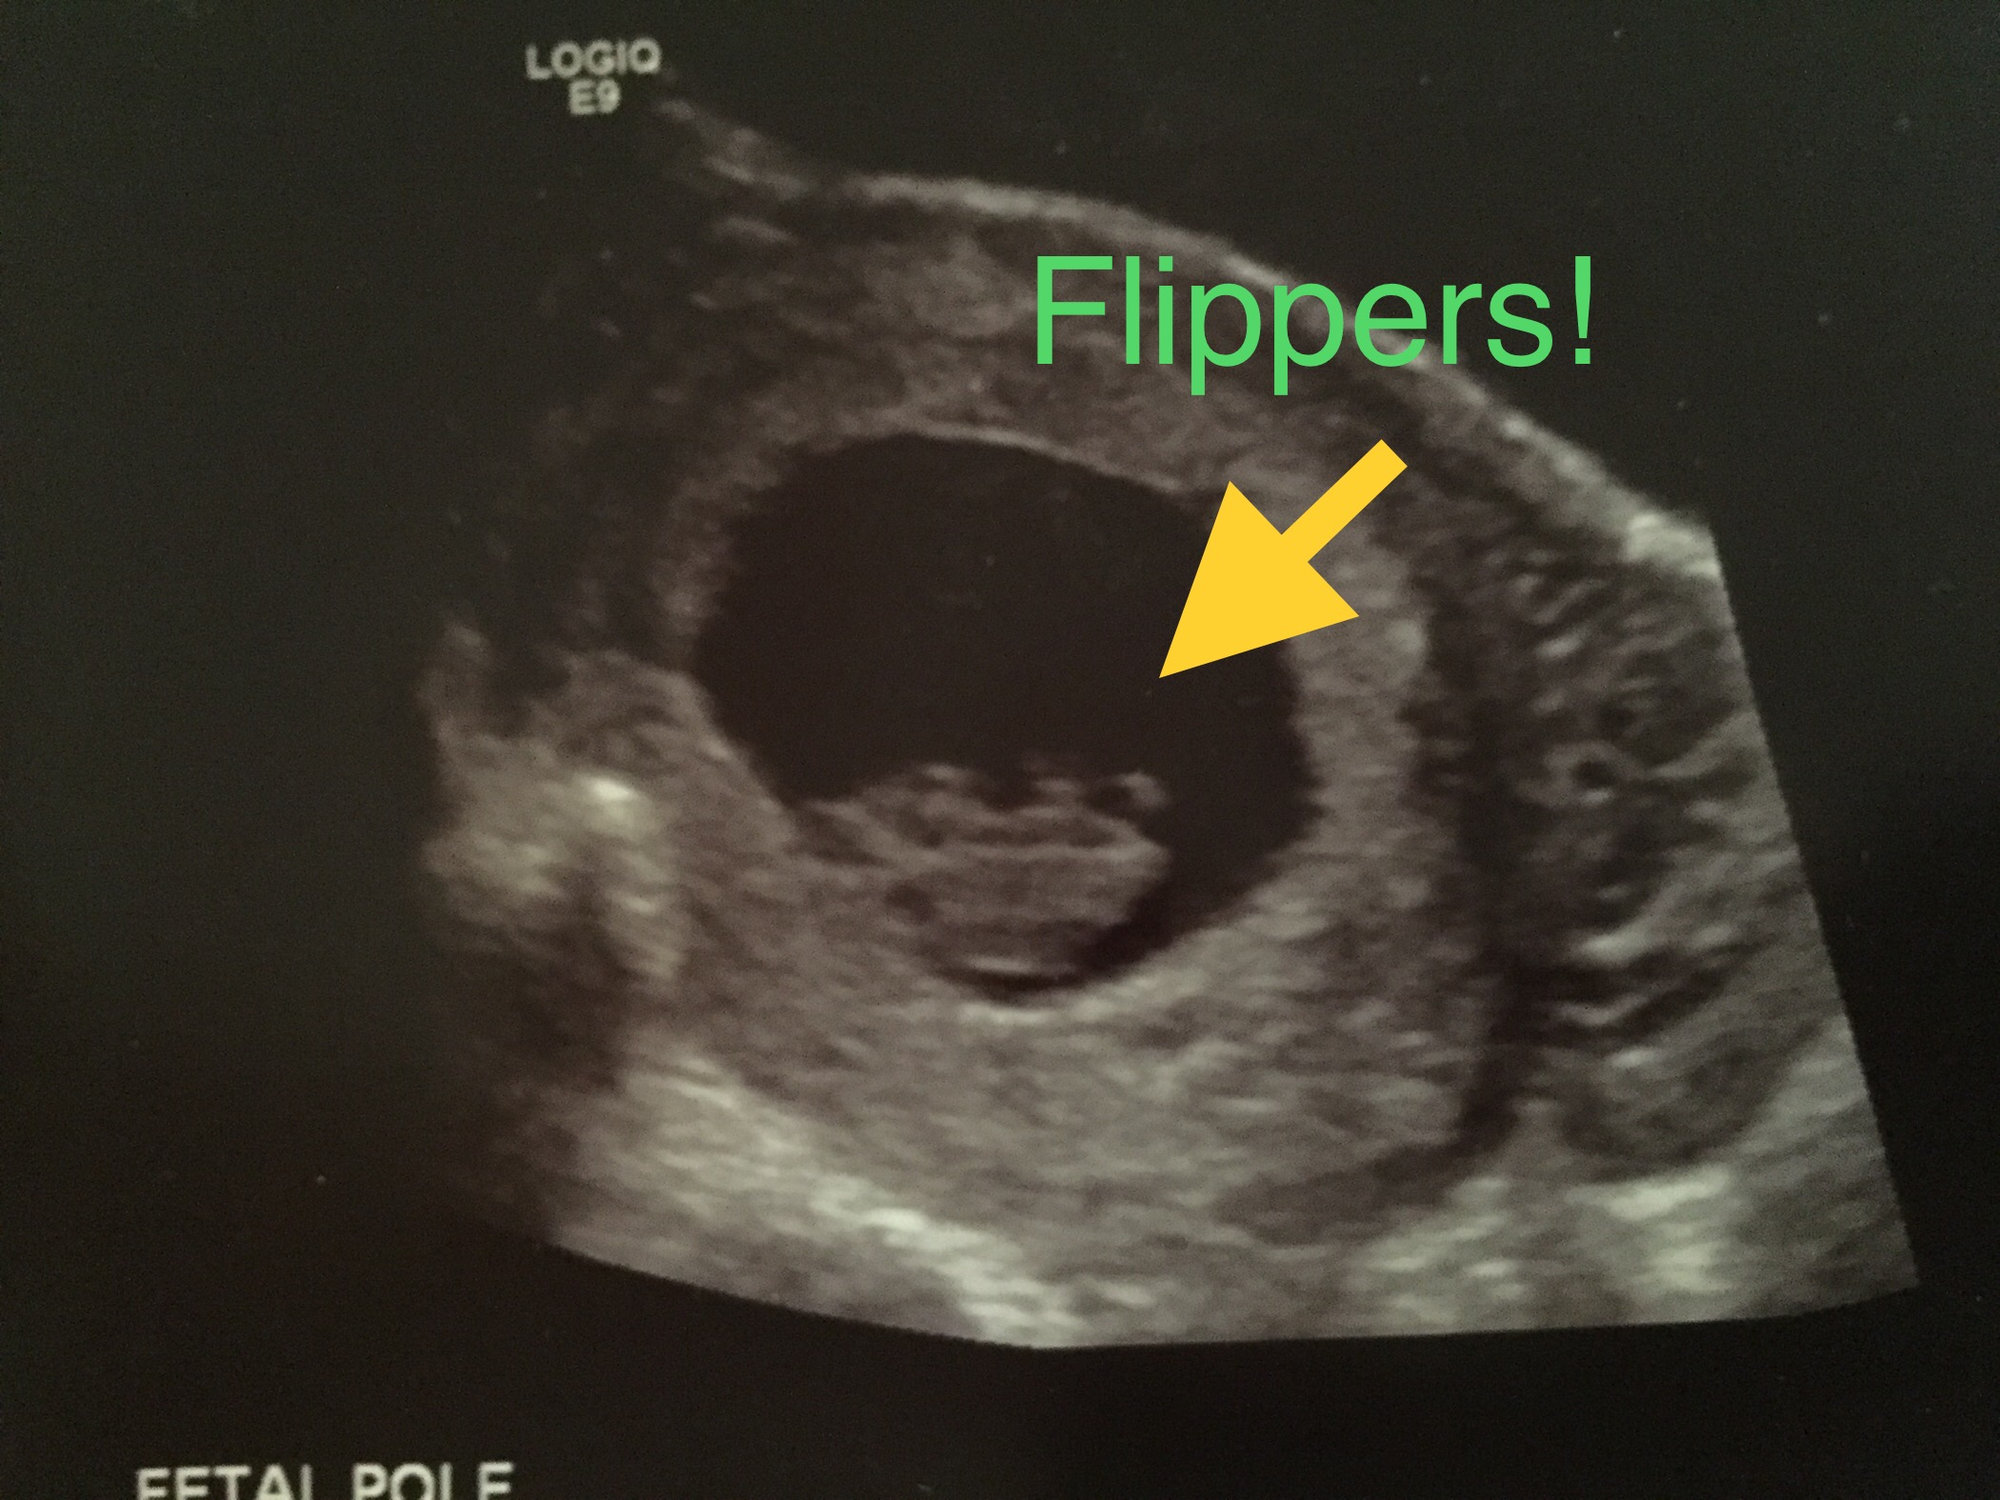

Hi everyone! My EDD is 7/1/2019, so I’m not sure if I’ll be here or in June. Here is our ultrasound photo from 8 weeks (transvaginal) a couple weeks ago. Heartbeat was 172bpm. Baby is the blob on the upper right, facing away.

Here is our ultrasound photo from 8 weeks (transvaginal) a couple weeks ago. Heartbeat was 172bpm. Baby is the blob on the upper right, facing away.